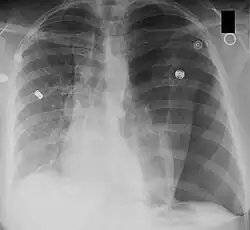

(a.p.)-Röntgenbild eines Spannungspneumothorax der linken Seite (im Bild rechts) mit Mediastinalshift nach rechts.